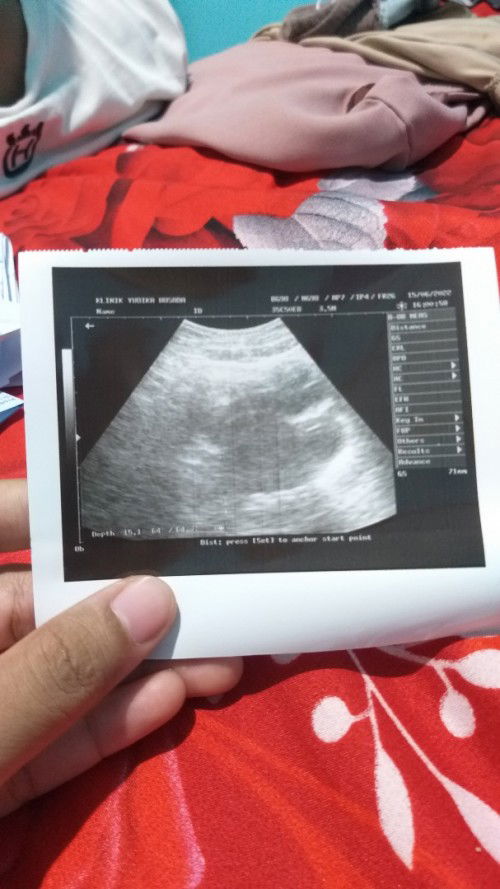

Bunda² aq mau sharing kehamilanku 6minggu kurang 1 hari,kalo malem jam 9 suka kelaperan udah ngemil sama minum susu kadang sampe jam 11 keatas ga bisa tidur.suka sakit perut bagian bawah ky cenut² kadang pinggang'a berasa nyeri+panas bunda ada ga ngrasain sama ky aku?#ingintahu apakah aman bun